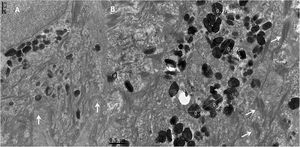

TEM demonstrated normal epidermal structures, such as desmosomes, cytokeratin filaments, basement membrane and hemidesmosomes (Figs. 3a and b). A high amount of melanosomes in keratinocytes was observed (Fig. 3b), which measured 0.38 to 0.67 nm, a variation in the form and size could also be observed (Figs. 3b, 4a and 5).

With high magnifications indentations in melanosomes’ outline (Fig. 4a and b) could be seen, as well as an irregular melanosomal contour was observed (Fig. 5), in contrast to normal melanosomes, which show a regular contour and an oval shape (Fig. 5 inset).